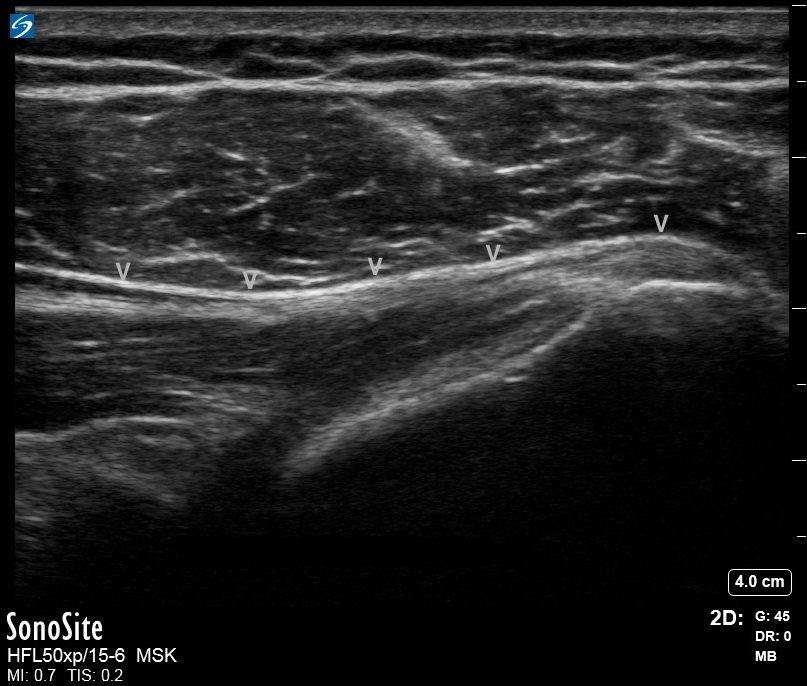

Image : Épaule : Muscle petit rond, insertion normale du tendon